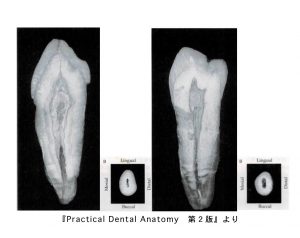

上顎小臼歯の中身

• 歯の外形を縮小した形。頬舌面からみると棍棒状で、隣接面からみると髄室は幅広く、根管は細い。

• 2根管性が多く認められる。

• 第一小臼歯では完全分岐根管の他に、不完全分岐根管、網状根管が第二小臼歯よりも多く認められる。

• 根管は根尖側1/3で細く、根管の尖端は頬側および舌側に湾曲することが多い。

下顎小臼歯の中身

• 歯の外形を縮小した形。

• 頬舌面からみると棍棒状で幅狭い。

• 隣接面からみると歯頸線直下で幅広く、根尖側1/3で細くなっている。

• 根管の尖端は根尖にまっすぐ向かうものと、湾曲するものがある。

• 根管の形態は単純根管および根尖分岐が多く認められる。また、一部には網状根管が認められる。